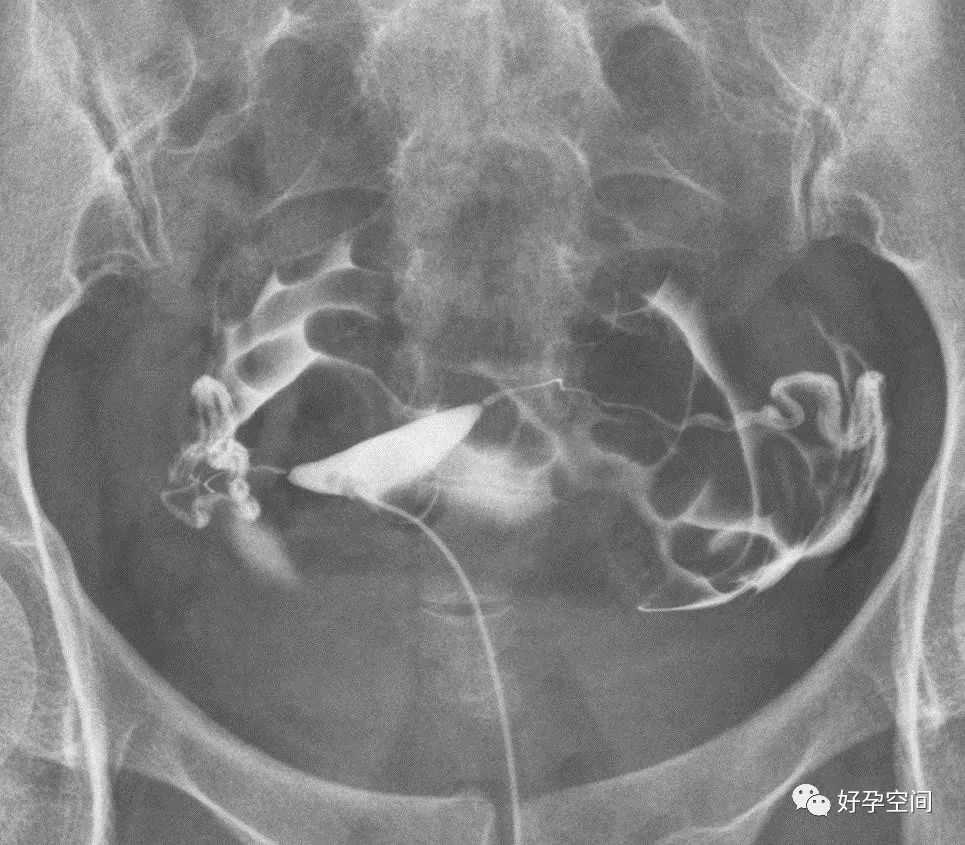

输卵管相